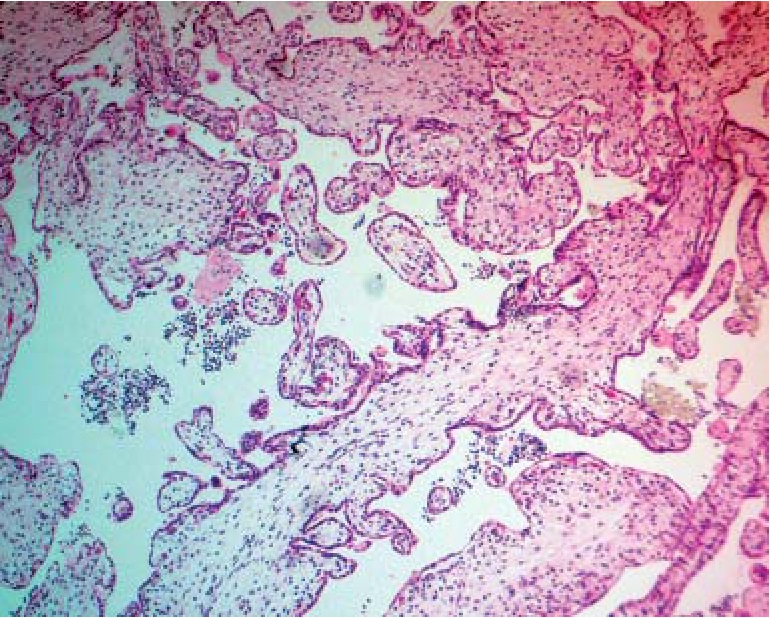

В остальной группе трисомий, в частности при трисомии по 13-й хромосоме, ведущим диагностическим признаком была выраженная гидропическая дистрофия стромы ворсин хориона с трансформацией их в крупные кистозные полости (цистерны) и полная аваскуляризация (рис. 2). Кроме того, в ряде случаев при трисомии по 13-й хромосоме отмечался выраженный фиброз ворсин хориона (рис. 3). Покровный хориальный эпителий был с резко выраженными признаками атрофии и имел вид тонкой узкой полоски. Наиболее выраженной кистозная трансформация ворсин была при трисомии по 16-й хромосоме, единичные ворсины напоминали картину, схожую с пузырным заносом.

Рис. 3. Фиброз ворсин хориона, атрофия хориального эпителия при трисомии по 13-й хромосоме. Окраска гематоксилином-эозином, ув. ×180